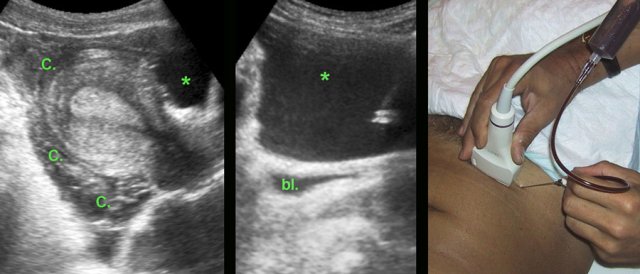

Luteal body bleeding mimicking an ectopic pregnancy

In

this young woman, US demonstrated a large quantity of clotted (C.) and liquified

blood (*) around the uterus, suspect for ectopic pregnancy. However, β-HCG levels in both urine and serum were extremely

low.

US guided puncture in the liquified part confirmed blood. (bl. = bladder)

Laparoscopy revealed severe bleeding from a luteal body, which was successfully coagulated.